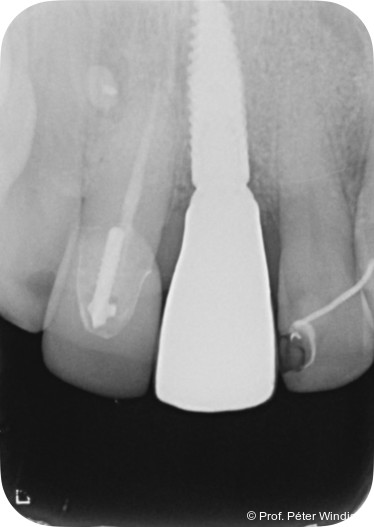

Radiologisch war ein signifikanter Knochenabbau um das Implantat zu verzeichnen (Abb. 2). Die klinische Untersuchung zeigte klassische Anzeichen einer periimplantären Entzündung: Bluten auf Sondieren (BOP+), erhöhte Sondierungstiefen (ST) und eine lokale Schwellung der Mukosa (Abb. 3–5). Das primäre Ziel war es, den Entzündungsprozess nicht chirurgisch zu stoppen und ein biologisches Milieu zu schaffen, das eine langfristige Stabilität ermöglicht. Der Implantataufbau wurde derzeit am Halsbereich zu dick ausgearbeitet und wies aus diesem Grund kein optimales Emergenzprofil auf. Nach der Eingliederung der definitiven prothetischen Versorgung kann es – insbesondere bei dicken suprakrestalen Weichgeweben – vorkommen, dass sich das Weichgewebe an die Kronenkontur adaptiert, was biologisch nicht immer gut toleriert wird. In der Folge kann es zu einer lokalen entzündlichen Reaktion kommen. Aus diesem Grund war zudem eine Umgestaltung der Krone vorgesehen.